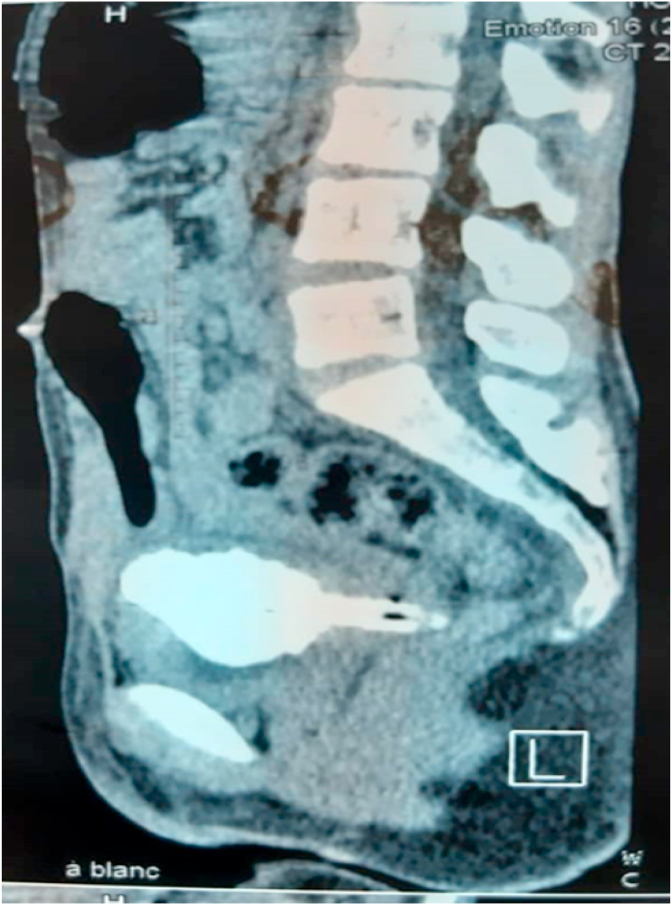

Fig. 2.

Computer tomography (CT) scan of the urinary tract showed a vesicovaginal invasion by a tubular foreign body strongly calcified in the bladder.